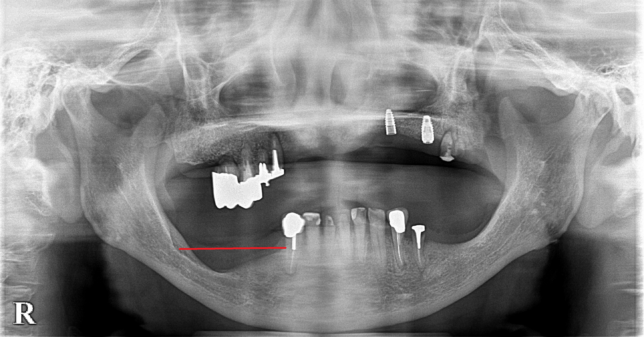

こちらのレントゲンをご覧ください。

現在

赤い線より下部分の骨が痩せています。7年前より骨の高さが減っているのが分かるでしょうか?

痩せてしまう原因は嚙み合わせなど色々あるのですが、このように入れ歯を使っていても骨が痩せてしまうことがあるのです。

この方の場合は、下の入れ歯をシリコン義歯に変えたことで、なんとか痛みから解放されましたが、普通の入れ歯ではまず無理だったと思います。

また、噛みあう上の歯の嚙み合わせも良くないので、今後治療して改善していく予定です。